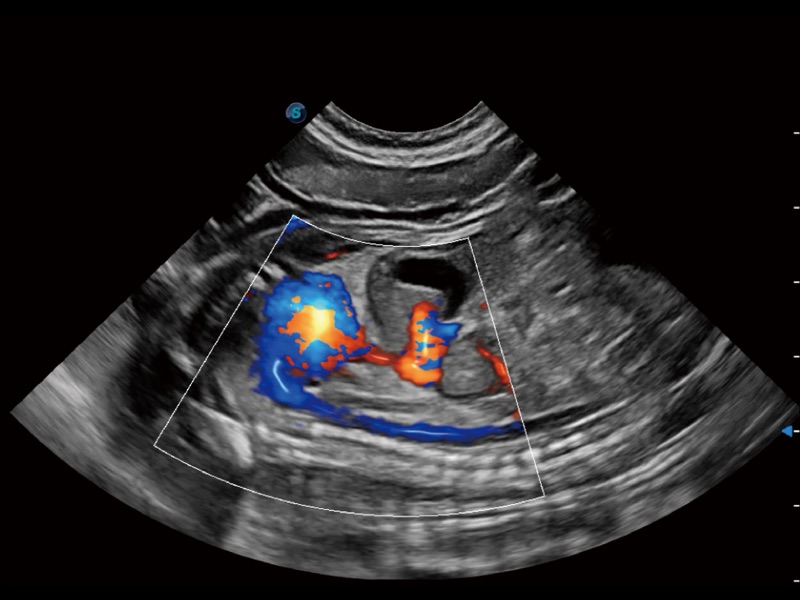

通过色彩血流和实时宽景相结合,可观察到完整的静脉或动脉的血流,方便医生检查。实时扫查过程中,如有任何操作失误也可以很容易地进行回扫擦除,而不会中断扫查。